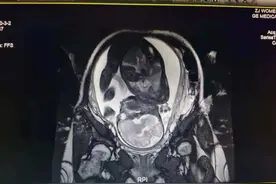

宫缩:子宫收缩(即宫缩),开始是不规则的,强度较弱,逐渐变得有规律,强度越来越强,持续时间延长,间隔时间缩短,如间隔时间在2—3分钟,持续50—60秒。宫缩是什么感觉:平时子宫摸起来软软的,当宫缩严重而频繁时,子宫就会变硬,会有腹部紧绷的感觉,甚至会痛。

宫缩就是指子宫的收缩。这是分娩过程中子宫的一个最重要的过程。假如没有宫缩,宝宝就没有办法生出来。宫缩过程中会有伴有腹部的疼痛,用手扪腹部的时候,会发现腹部有一个很硬的球,那就是正在收缩的子宫。由于宫缩都是一阵一阵的,腹痛也是一阵一阵的,所以我们把这种疼痛称为“阵痛”。